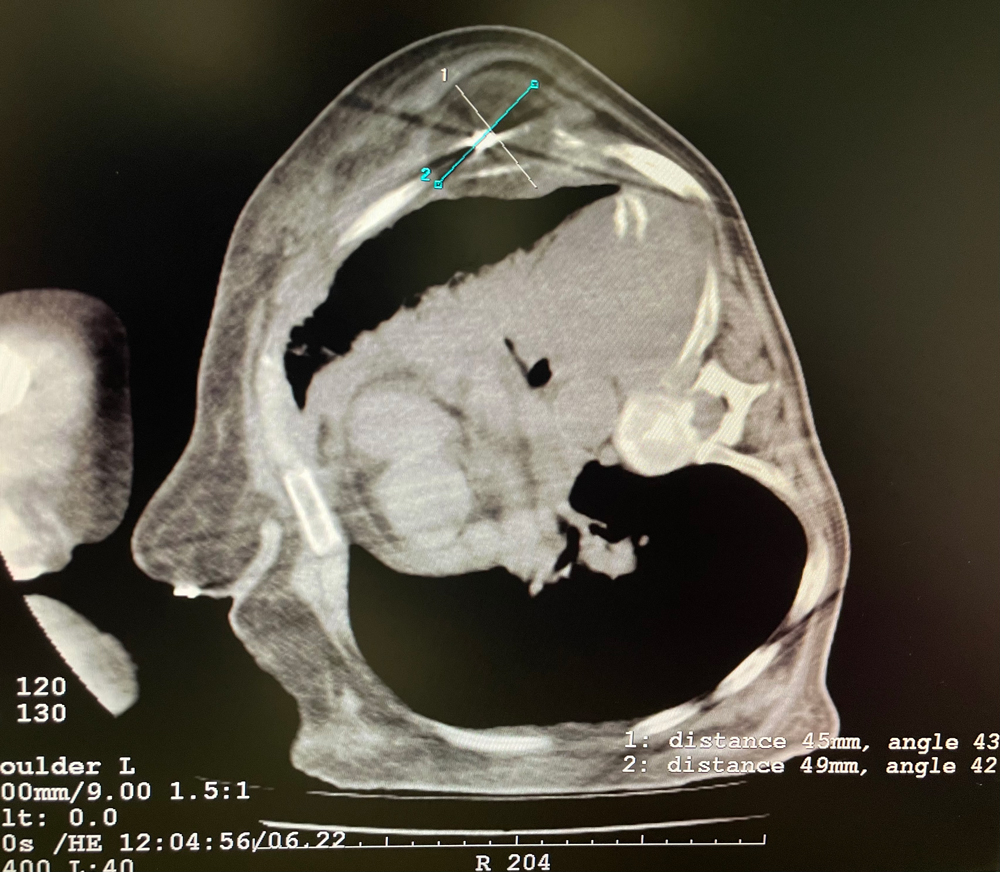

女,56岁,肺转移瘤,骶骨、左侧肋骨各一转移灶,病灶大小均为5cm。骶骨转移灶、肋骨转移灶各进行2个冻融循环。患者术后状况良好。